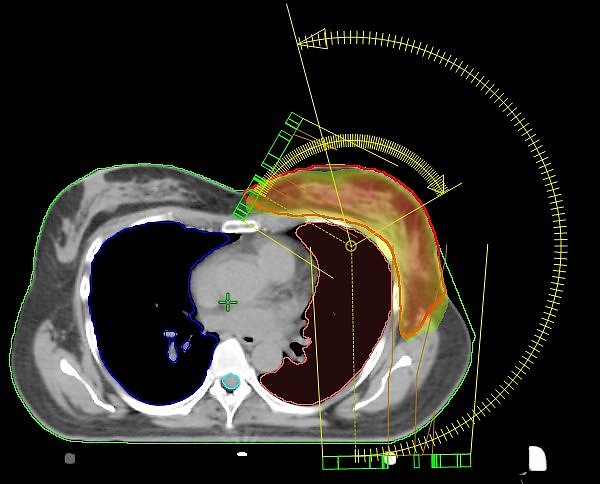

Einzigartig in Nordhausen: VMAT-Bewegungsbestrahlungstechnik mit 2 Bögen (Nordhäuser Standardtechnik); der Hochdosisbereich erfasst ausschließlich das Zielvolumen und die umgebenden Risikoorgane werden geschont.